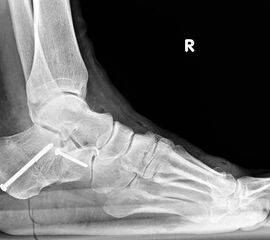

Die stehende OSG ap -Aufnahme kann zunächst das fibulocalcaneare Impingement und im Endstadium laterale OSG Arthrose oder Valgus-Tilt des Talus zeigen.

Radiologisches Beispiel einer fixierten Planovalgus Deformität Stadium III, 51 jähriger Patient. Stehendes präoperatives Röntgenbild und 1 Jahr postoperatives Röntgenbild des Fußes seitlich. Die Korrektur der Deformität umfaßte eine leicht korrigierende U

Abbildung 12

Im Stadium III der Tibialis posterior Sehneninsuffizienz bei fixierter Deformität und/oder erheblich eingeschränkter Inversion im USG aber stabilen und flexiblen Chopart-Gelenk und weniger als 10° fixierter Vorfußsupination eine in-situ oder leicht korrigierende USG-Arthrodese indiziert. Der Vorteil einer isolierten USG-Arthrodese gegenüber einer Triple- oder Double-Arthrodese ist die verbleibende, funktionell wichtige Beweglichkeit in der Chopart-Gelenkreihe. Um einem persistierenden fibulocalcanearem Impingement sicher vorzubeugen, sollte die USG-Arthrodese in maximal 5° Valgus- oder sogar Neutralposition erfolgen. Zur Prophylaxe eines Rezidivs wird die USG-Arthrodese zudem häufig mit einer medialisierende Tuber calcanei Osteotomie und / oder einem FDL-Transfer kombiniert (Abb. 12).